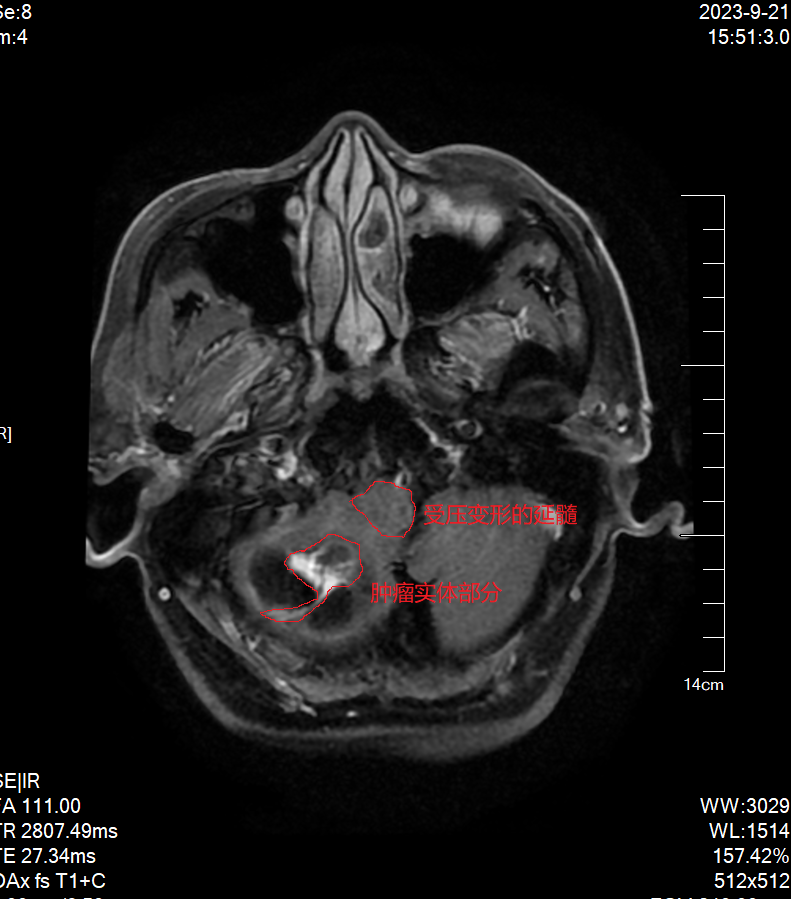

头颅MRI提示宋伯右侧小脑巨大囊实性占位,血管母细胞瘤可能性大,肿瘤实体部分不规则且靠近延髓,延髓受压变形严重,脑疝倾向,随时有生命危险。

术前头颅MRI示肿瘤压迫延髓

术前头颅MRI示肿瘤实体部分紧邻延髓